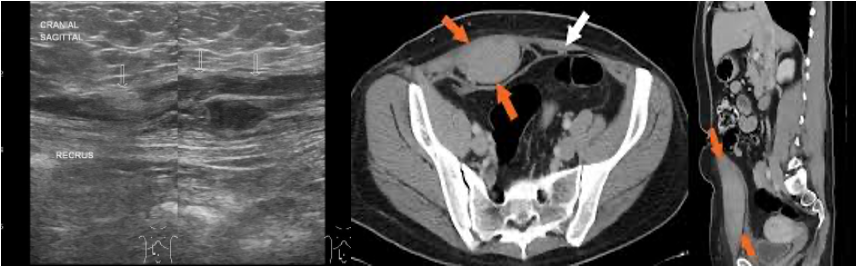

- Diagnosis: U/S.